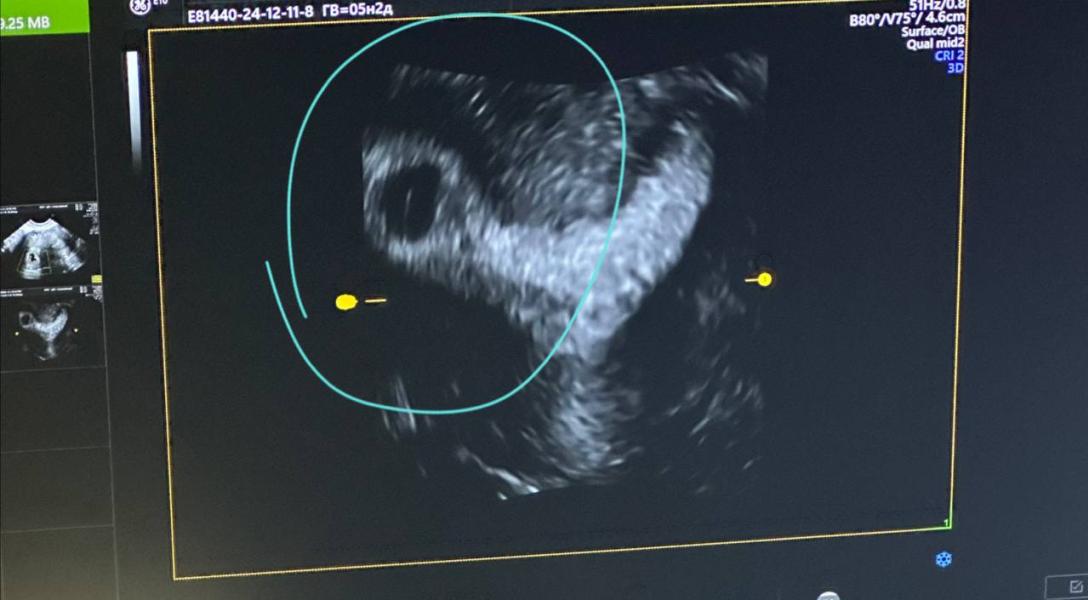

Клинический случай, смотрите какая седловидная матка 🐎

Результат на фото! Все таки нравится мне PRP- процедура в криоПЭ. Будем выступать в январе с докладом на эту тему))